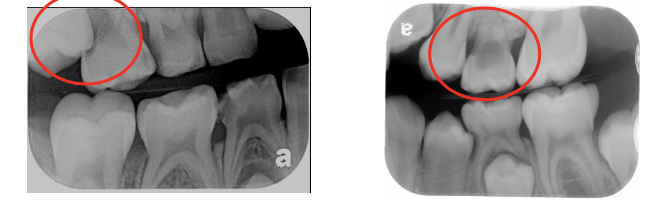

1. Indications and Rationale for Extraction of Deciduous Teeth (IRET)

IRET – Infections, Restore, Extraction, Trauma

Infections (odontogenic infections, irreversible pulpitis, pulpal necrosis)

Restore (hopeless prognosis, internal resorption, external resorption)

Extraction due to severe resorption (ectopic eruption, retained roots)

Trauma-related infection (alveolar abscess)

A